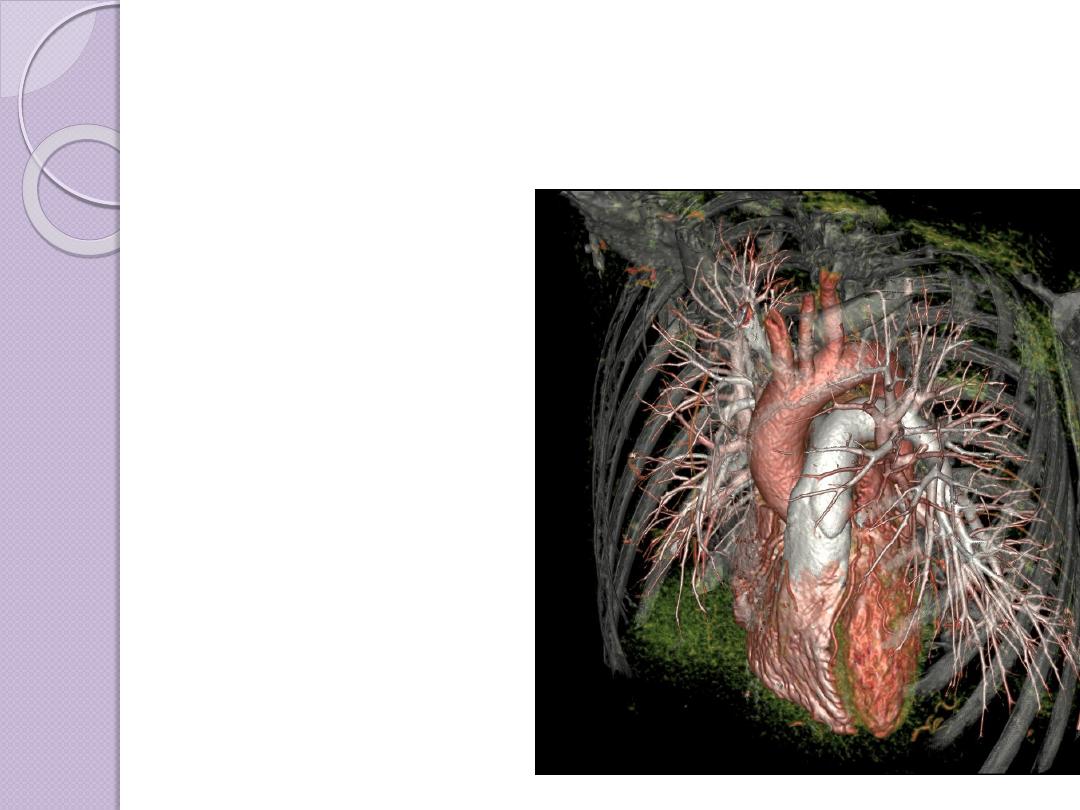

ADVANCES OF CT

Faster CT machines, due to multidetector

capabilities, have made imaging of

the

and

very

practical in a number of clinical

settings.The faster capability has allowed

the imaging of the heart with minimal

involuntary motion, which creates

3D

RECONSTRUCTION

Multiplanar

reconstruction the

simplest method of

reconstruction. A

volume is built by

stacking the axial slices